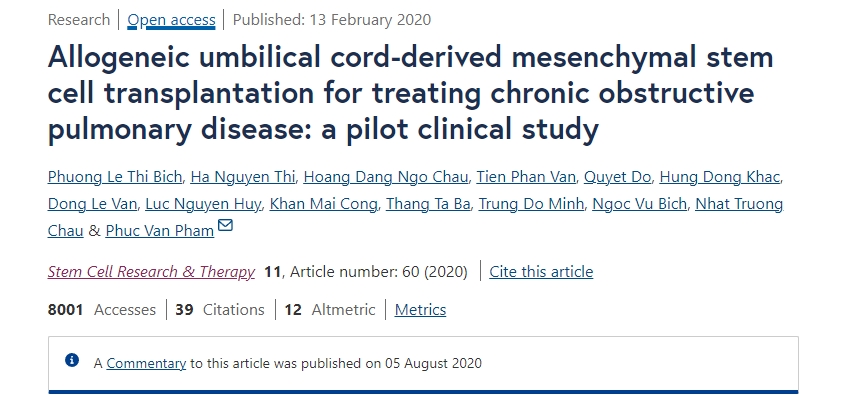

2020年2月13日,越南胡志明市范行總醫(yī)院在行業(yè)期刊《干細(xì)胞研究與治療》上發(fā)表了一篇關(guān)于《同種異體臍帶間充質(zhì)干細(xì)胞移植治療慢性阻塞性肺病:一項(xiàng)初步臨床研究》的研究成果。【4】

共有20名患者入組。根據(jù)??全球阻塞性肺病倡議 (GOLD) 分類,9名患者為C期,11名患者為D期。

安全性評(píng)估:UC-MSC輸注耐受性良好,所有患者在研究或藥物輸注過(guò)程中均未觀察到嚴(yán)重或臨床顯著的不良事件。

綜上所述,未發(fā)生與UC-MSC給藥相關(guān)的輸注毒性、死亡或嚴(yán)重不良事件。接受UC-MSC移植的患者的改良醫(yī)學(xué)研究委員會(huì)評(píng)分、COPD評(píng)估測(cè)試和加重次數(shù)均顯著降低。

結(jié)論:系統(tǒng)性UC-MSC治療對(duì)中度至重度COPD患者似乎是安全的,可以顯著改善他們的生活質(zhì)量,并為后續(xù)的細(xì)胞治療研究提供基礎(chǔ)。